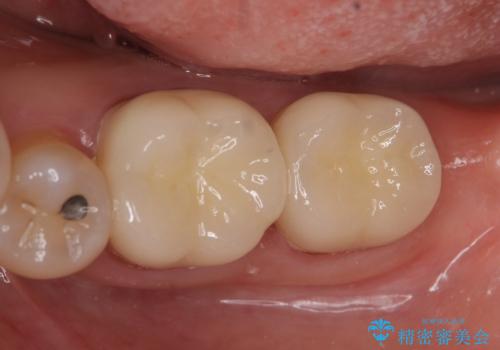

症状の消失を確認後、オールセラミッククラウンによる補綴を行いました。

今回用いたオールセラミッククラウンは、ジルコニアフレームという白い素材の上にセラミックを盛っているため審美性が非常に高いのが特徴です。

またジルコニアは人工ダイヤモンドの材料にも使われているほど高い強度を持っており、そのためオールセラミッククラウンは審美性だけでなく、奥歯やブリッジの補綴も可能とするクラウンです。